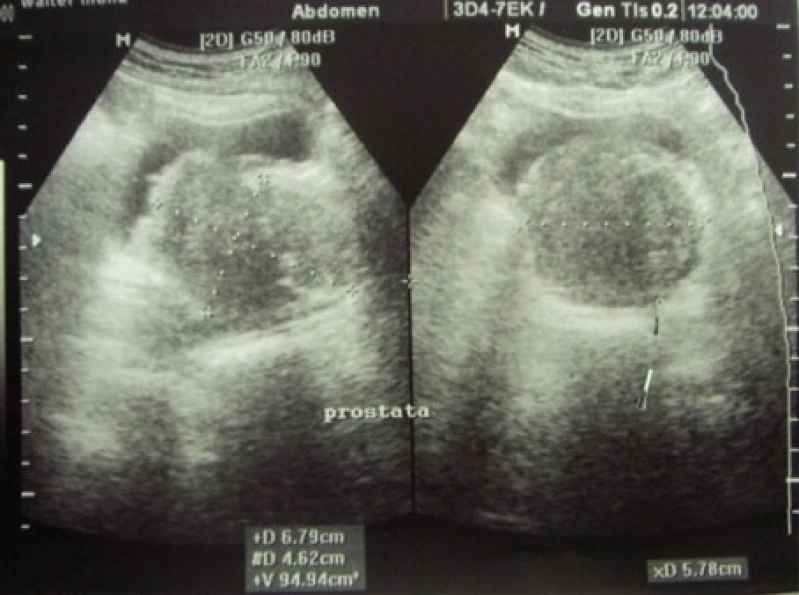

A ultrassonografia de próstata é um exame não invasivo que utiliza ondas sonoras de alta frequência para produzir imagens da próstata. É um exame importante para detectar alterações na próstata, como o aumento de tamanho, nódulos ou tumores. O exame é realizado com o paciente deitado de barriga para baixo e um gel é aplicado na região do abdômen. O médico urologista utiliza um aparelho de ultrassom para visualizar a próstata e avaliar sua estrutura. O exame é rápido e indolor, e não requer preparação especial. É recomendado para homens a partir dos 50 anos ou mais cedo em casos de histórico familiar de câncer de próstata. A DK Urologistas oferece esse exame com equipamentos modernos e profissionais especializados para garantir a precisão do diagnóstico. Agende sua consulta e cuide da sua saúde!